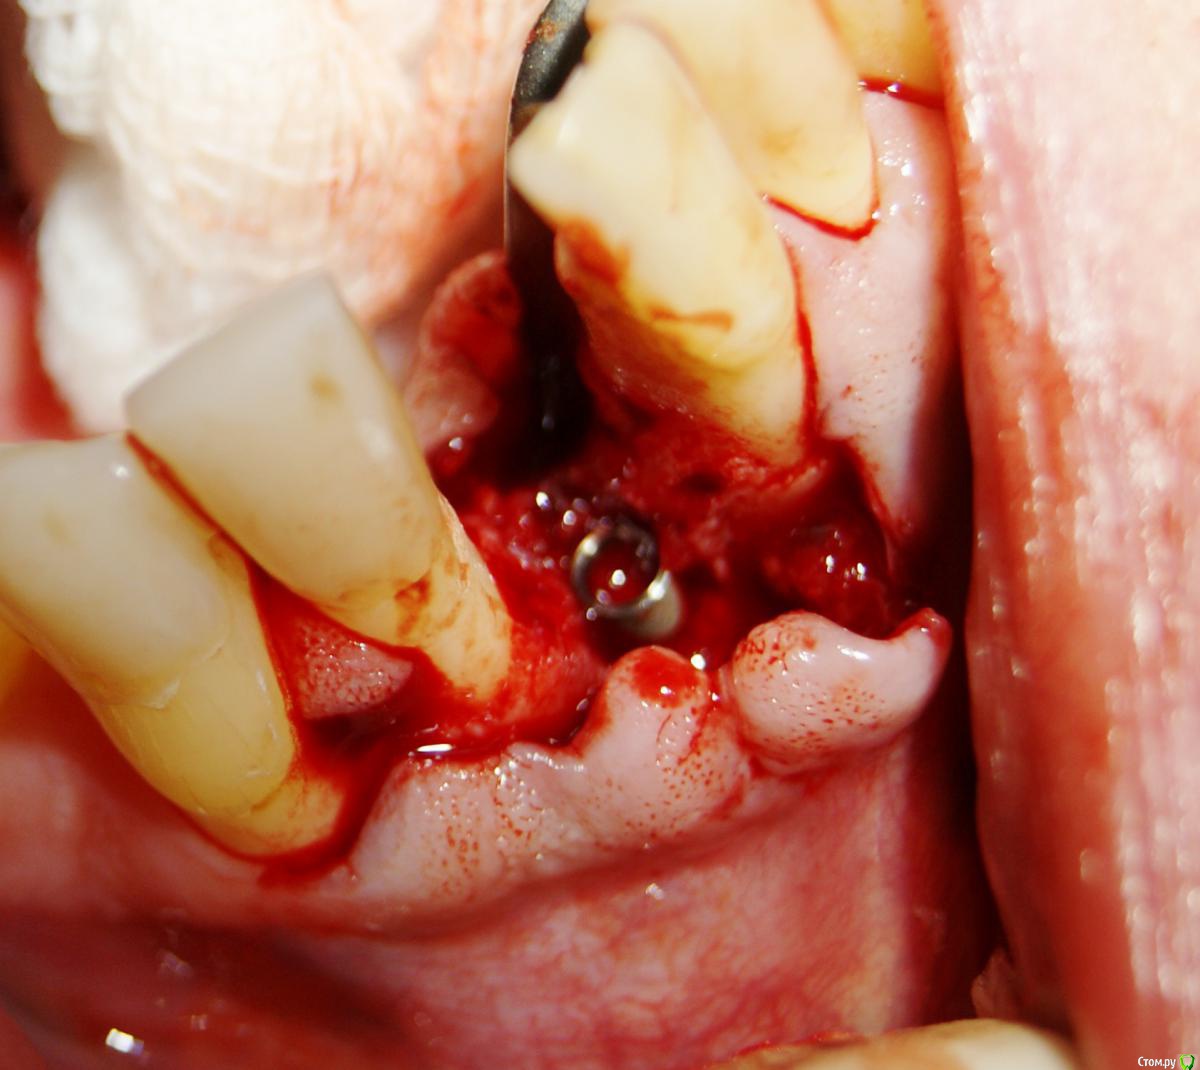

Jurai Опубликовано 25 декабря, 2016 Поделиться Опубликовано 25 декабря, 2016 *Предупреждение: фото на "мыльницу", не все этапы удались, но я работаю над этим) Вот пациент. Приятнейший, во всех отношениях, с негативным отношениям к мостовидным конструкциям. Полтора года лечил 41з по поводу периодонтита: толку не вышло. Удалил у широко известного многим стоматологам, особенно выпускам последних годов, доктора с ученой степенью. После удаления 4 месяца, по КТ область вполне достойно выглядит. Вот с чем пришел, обычное дело, все прилично: Раскрываю, а там между тонкими кортикалками мягко и упруго - резидуальная, фото нет. Открываю сильнее чем обычно, с расстройства не особо удачно. Кюретаж : Вид после, ушла вестибулярная кортикальная вместе с кистой: Сверлим 2,0, позиционердля рентген-контроля Имплантат ADIN UNP2,75Х11,5мм Ауто, джейсон коллагенфлис (что было под рукой) Швы. Контроль, перещелкивать не стали. В общем, понравился имплантат, для себя пометку кюретажить тщательнее, не надеяться, что организм все переварит. 1 9 Ссылка на комментарий